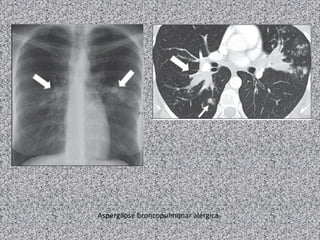

Bronquiectasias com distribuição bilateral e

predomínio nos lobos superiores são mais

frequentemente encontradas em pacientes com

ABPA, fibrose cística e fibrose relacionada com

sarcoidose e silicose.

Aspergilose broncopulmonar alérgica